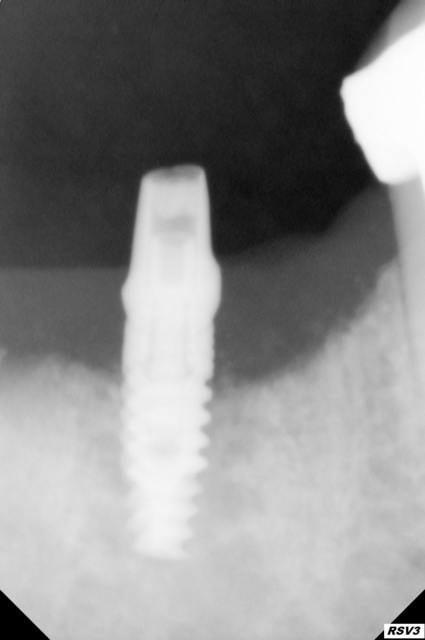

c'est du 4.2*10 mm pour replacer l’équivalent d'une molaire ....je ne pense pas que l’échec soit strictement lié au cantilever ou à une surocc .

alphabio ICE

au vue de la radio et des info qu'on a, cela ne semble pas être une périimplantite infectieuse. plutôt un implant mal osteointegré, ou un problème de surface.

non osteo integré : j'ai fait des tests à la percussion, sondage et radios ensuite j'ai vissé les piliers à 30 N sans douleurs ....

ce qui est étonnant, c'est de trouver du ciment dans les spires..

Eh oui c'est sur ce fait que je voulais attirer l'attention comment expliquer que je retrouve du ciment aussi apicalement alors que sur les différents clichés on voit pas de signes

Peut-être que comme le dit azerty06 l'implant semblait être ostéo-intégré mais ne l'était pas. Ca pourrait expliquer du ciment aussi bas.